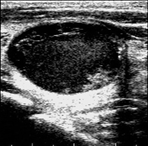

Figure 6 illustrates the segmentation outcomes attained with different neural networks using the same dataset. The enhanced U-Net network proposed in this study is evaluated alongside expert gold standards, Swin-Unet, U-Net, and other well-known network models. The segmentation results from the Swin-Unet network show jagged edges and less smooth nodule edge segmentation, leading to suboptimal outcomes. In the case of U-Net, there are evident under-segmentations with significant discrepancies in the segmented area of some nodules, resulting in inaccurate segmentation results. However, the use of the improved U-Net network introduced in this research produces smoother edges of the segmented thyroid nodules, and the edge contours more closely align with those of the expert gold standard. Moreover, the errors in shape and segmented area are smaller compared to those seen with U-Net and Swin-Unet. The findings suggest that the improved U-Net network provides superior performance in thyroid nodule segmentation.

(c) Swin-Unet segmentation outcome

(d) U-Net segmentation outcome

(e) Segmentation results after the improvements in this study

Figure 6. Ultrasound image segmentation results of thyroid nodules using different networks